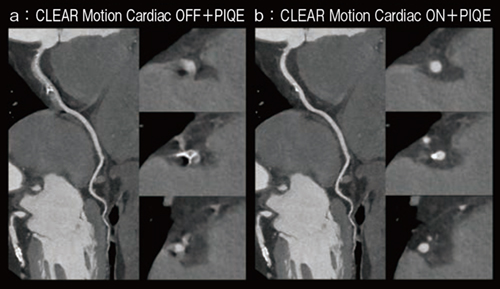

図4は,1心拍で心電図同期撮影した冠動脈石灰化症例(HR:77)である。CLEAR Motion Cardiacの適用により,心拍動に伴うモーションアーチファクトが低減され,冠動脈構造や石灰化をより明瞭に描出できており,確信度の高い診断への寄与や,心拍数や不整脈など,患者背景に左右されない検査ワークフローが期待できる。

図4 冠動脈石灰化症例(HR:77)

a:CLEAR Motion Cardiac OFF+PIQE

b:CLEAR Motion Cardiac ON+PIQE

(画像ご提供:藤田医科大学病院様)